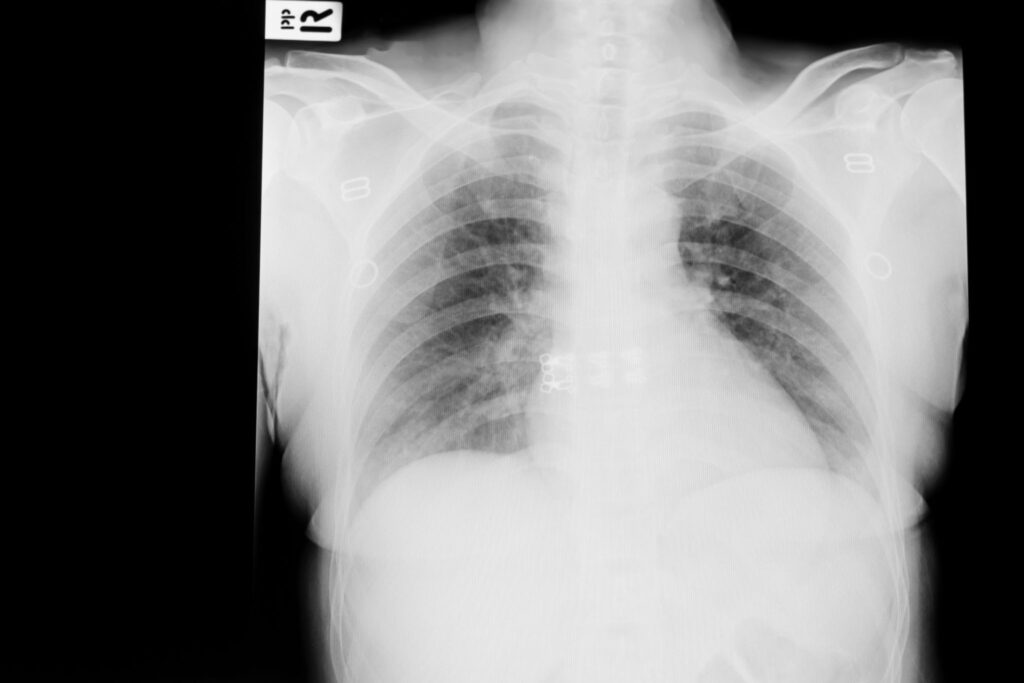

- Chest X-ray

- Confirms the presence and extent of lung infection.